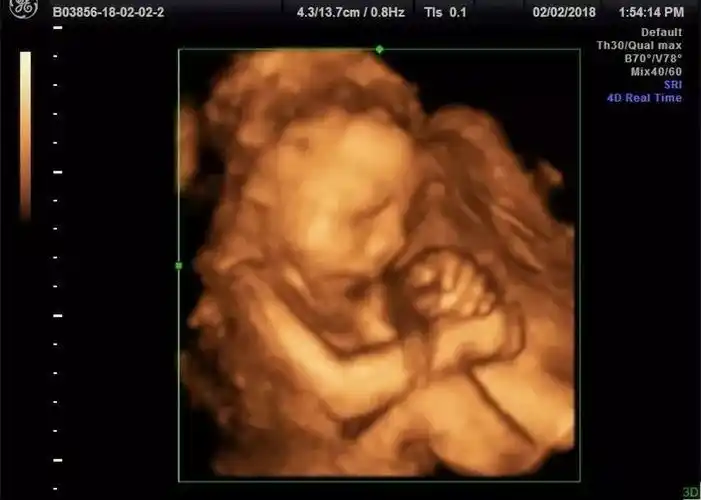

怀七个月做的四维,哈哈,宝妈们看看这是男孩女孩

四维彩超看男女 - 百度宝宝知道

脊柱串珠是女宝平行排列是男宝的说法是真的吗